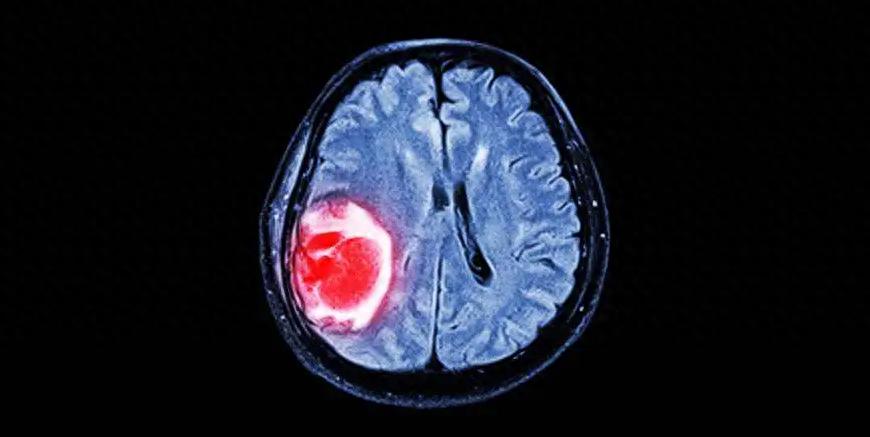

1. Gliomas

Gliomas are the most common type of brain tumor, accounting for 80% of primary intracranial malignant tumors.

Gliomas can be classified into grades I–IV, with grades I and II being low-grade gliomas, and grades III and IV being high-grade gliomas.

Gliomas can also be subdivided into specific pathological types, such as grade I subependymoma; grade II astrocytoma and oligodendroglial tumors; grade III anaplastic astrocytoma and anaplastic oligodendroglial tumors; and grade IV glioblastoma, among others.

As the grade increases, the malignancy of the tumor progressively rises.